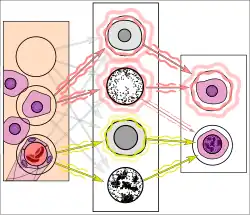

![Breast cancer prediction by AI.[17]](./_assets_/Histopathology_of_tumor_identification_by_AI.png) Breast cancer prediction by AI.[17]

Breast cancer prediction by AI.[17]